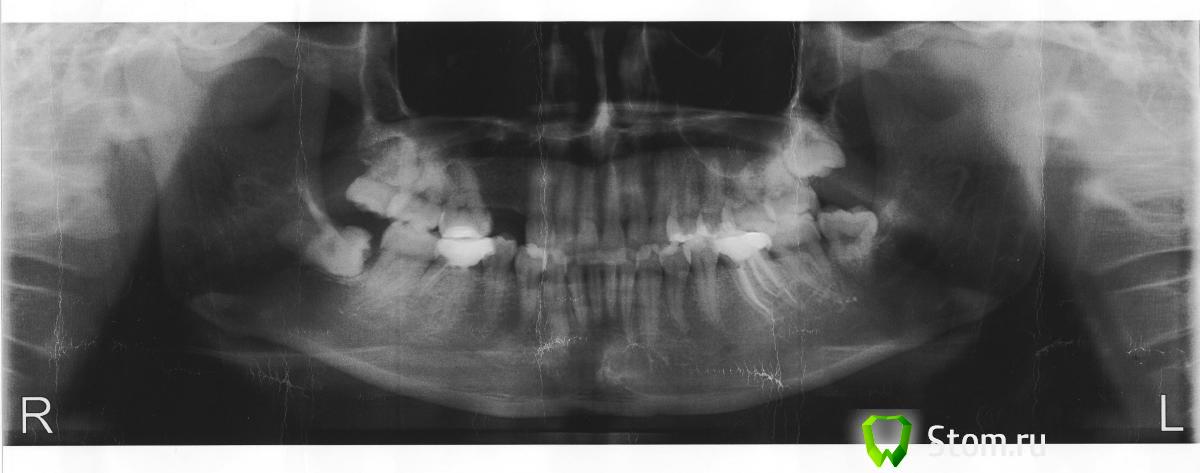

cerrone Опубликовано 13 марта, 2012 Поделиться Опубликовано 13 марта, 2012 Уважаемые, стоматологи!Помогите определиться можно ли установить импланты. У меня отсутствуют 2 верхних зуба, но прошло уже довольно много времени и, как мне объяснили, для установки имплантов костного материала недостаточно, как собственно и места, поскольку зубы уже разошлись и посоветовали обычное протезирование. В другой клинике, врач решил, что проблем по этой части никаких нет и был готов взяться за импланатацию. У третьего специалиста сомнения возникли, предложил синус-лифтинг, но честно признался, что опыт у него небольшой. Город у нас маленький, специалистов немного и то у всех разные мнения и возможности. Как быть, какие показания по снимку? Спасибо заранее. Ссылка на комментарий

Bier Опубликовано 14 марта, 2012 Поделиться Опубликовано 14 марта, 2012 ну там по коронке места ровно на 1 премоляр. Сиунслифтинг там не нужен. Но есть одна проблема - выдвинулся нижний зуб, с ним тоже нужно что-то делать. Ссылка на комментарий

Doc Опубликовано 16 марта, 2012 Поделиться Опубликовано 16 марта, 2012 Кости там более чем достаточно и грамотнее всего было бы делать имплантацию. Но если город маленький и специалистов нет, то может быть стоит задуматься о выборе между более или менее качественным мостом и не очень предсказуемой имплантацией при отсутствии надежных специалистов. Выбирать Вам по Вашим возможностям. Ссылка на комментарий

Dr. Surkin Опубликовано 17 марта, 2012 Поделиться Опубликовано 17 марта, 2012 ну там по коронке места ровно на 1 премоляр. Сиунслифтинг там не нужен. Но есть одна проблема - выдвинулся нижний зуб, с ним тоже нужно что-то делать. +1Костной ткани по высоте достаточно, так что синус-лифт не нужен, а вот про толщину кости по этому снимку ничего не скажешь. Если делать мост, то даю 95% вероятности, что вам удалят нервы из клыка и первого моляра.Если костной ткани по толщине будет все-таки достаточно для установки имплантата, то в современных условиях депульпировать и точить зубы под мост - варварство, да еще и по цене сопоставимое с имплантацией. Дополнительно - Вам необходимо удалить нижние зубы мудрости. Ссылка на комментарий

Dr. Surkin Опубликовано 18 марта, 2012 Поделиться Опубликовано 18 марта, 2012 Спасибо большое всем ответившим. Один врач сказал, что расстояния для одной коронки много, а для двух уже мало и лучше делать мост.А зачем удалять нижние зубы мудрости и что обычно делают с выдвинувшимися нижними зубами, обтачивают? Нижние 8-ки удалить для оздоровления полости рта. По поводу выдвинувшегося нижнего 5-го справа . Есть два варианта:1) Попробовать ортодонтически внедрить зуб2) Подточить зуб по высоте, что в зависимости от степени стачивания может повлечь за собой: удаление нерва +/- вмешательство на десне для увеличения клинической коронки зуба +/- последующее изготовление искусственной коронки Ссылка на комментарий